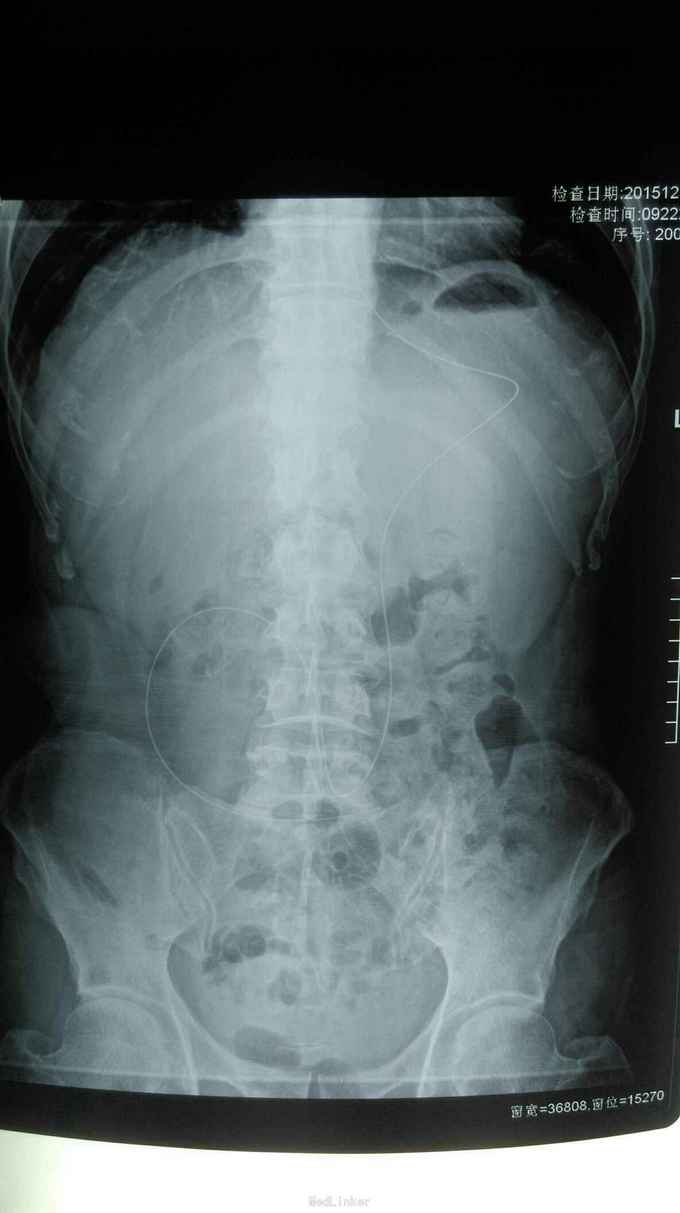

诊断: 中医诊断: 胃癌 痰气交阻 西医诊断:残胃癌 中分化腺癌 浸润型 Lauren分型:肠型 肝转移 胃周 腹腔淋巴结转移 多疗程化疗后 空肠营养管植入术后: 呕吐原因待查 中度贫血 右半结肠癌(术后、化疗后) 2型糖尿病 治疗:入院给予查腹部立位片未见液气平面,给予止吐,输血纠正贫血,营养支持,中医中药扶助正气治疗,行动脉介入化疗药灌注(奥沙利铂150mg+氟尿密啶0.75g),肝转移灶(吡柔比星20mg+碘化油6ml)栓塞治疗。